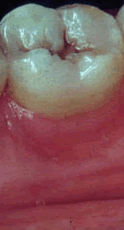

Pase el ratón para ver bolsa, recesión y movilidad